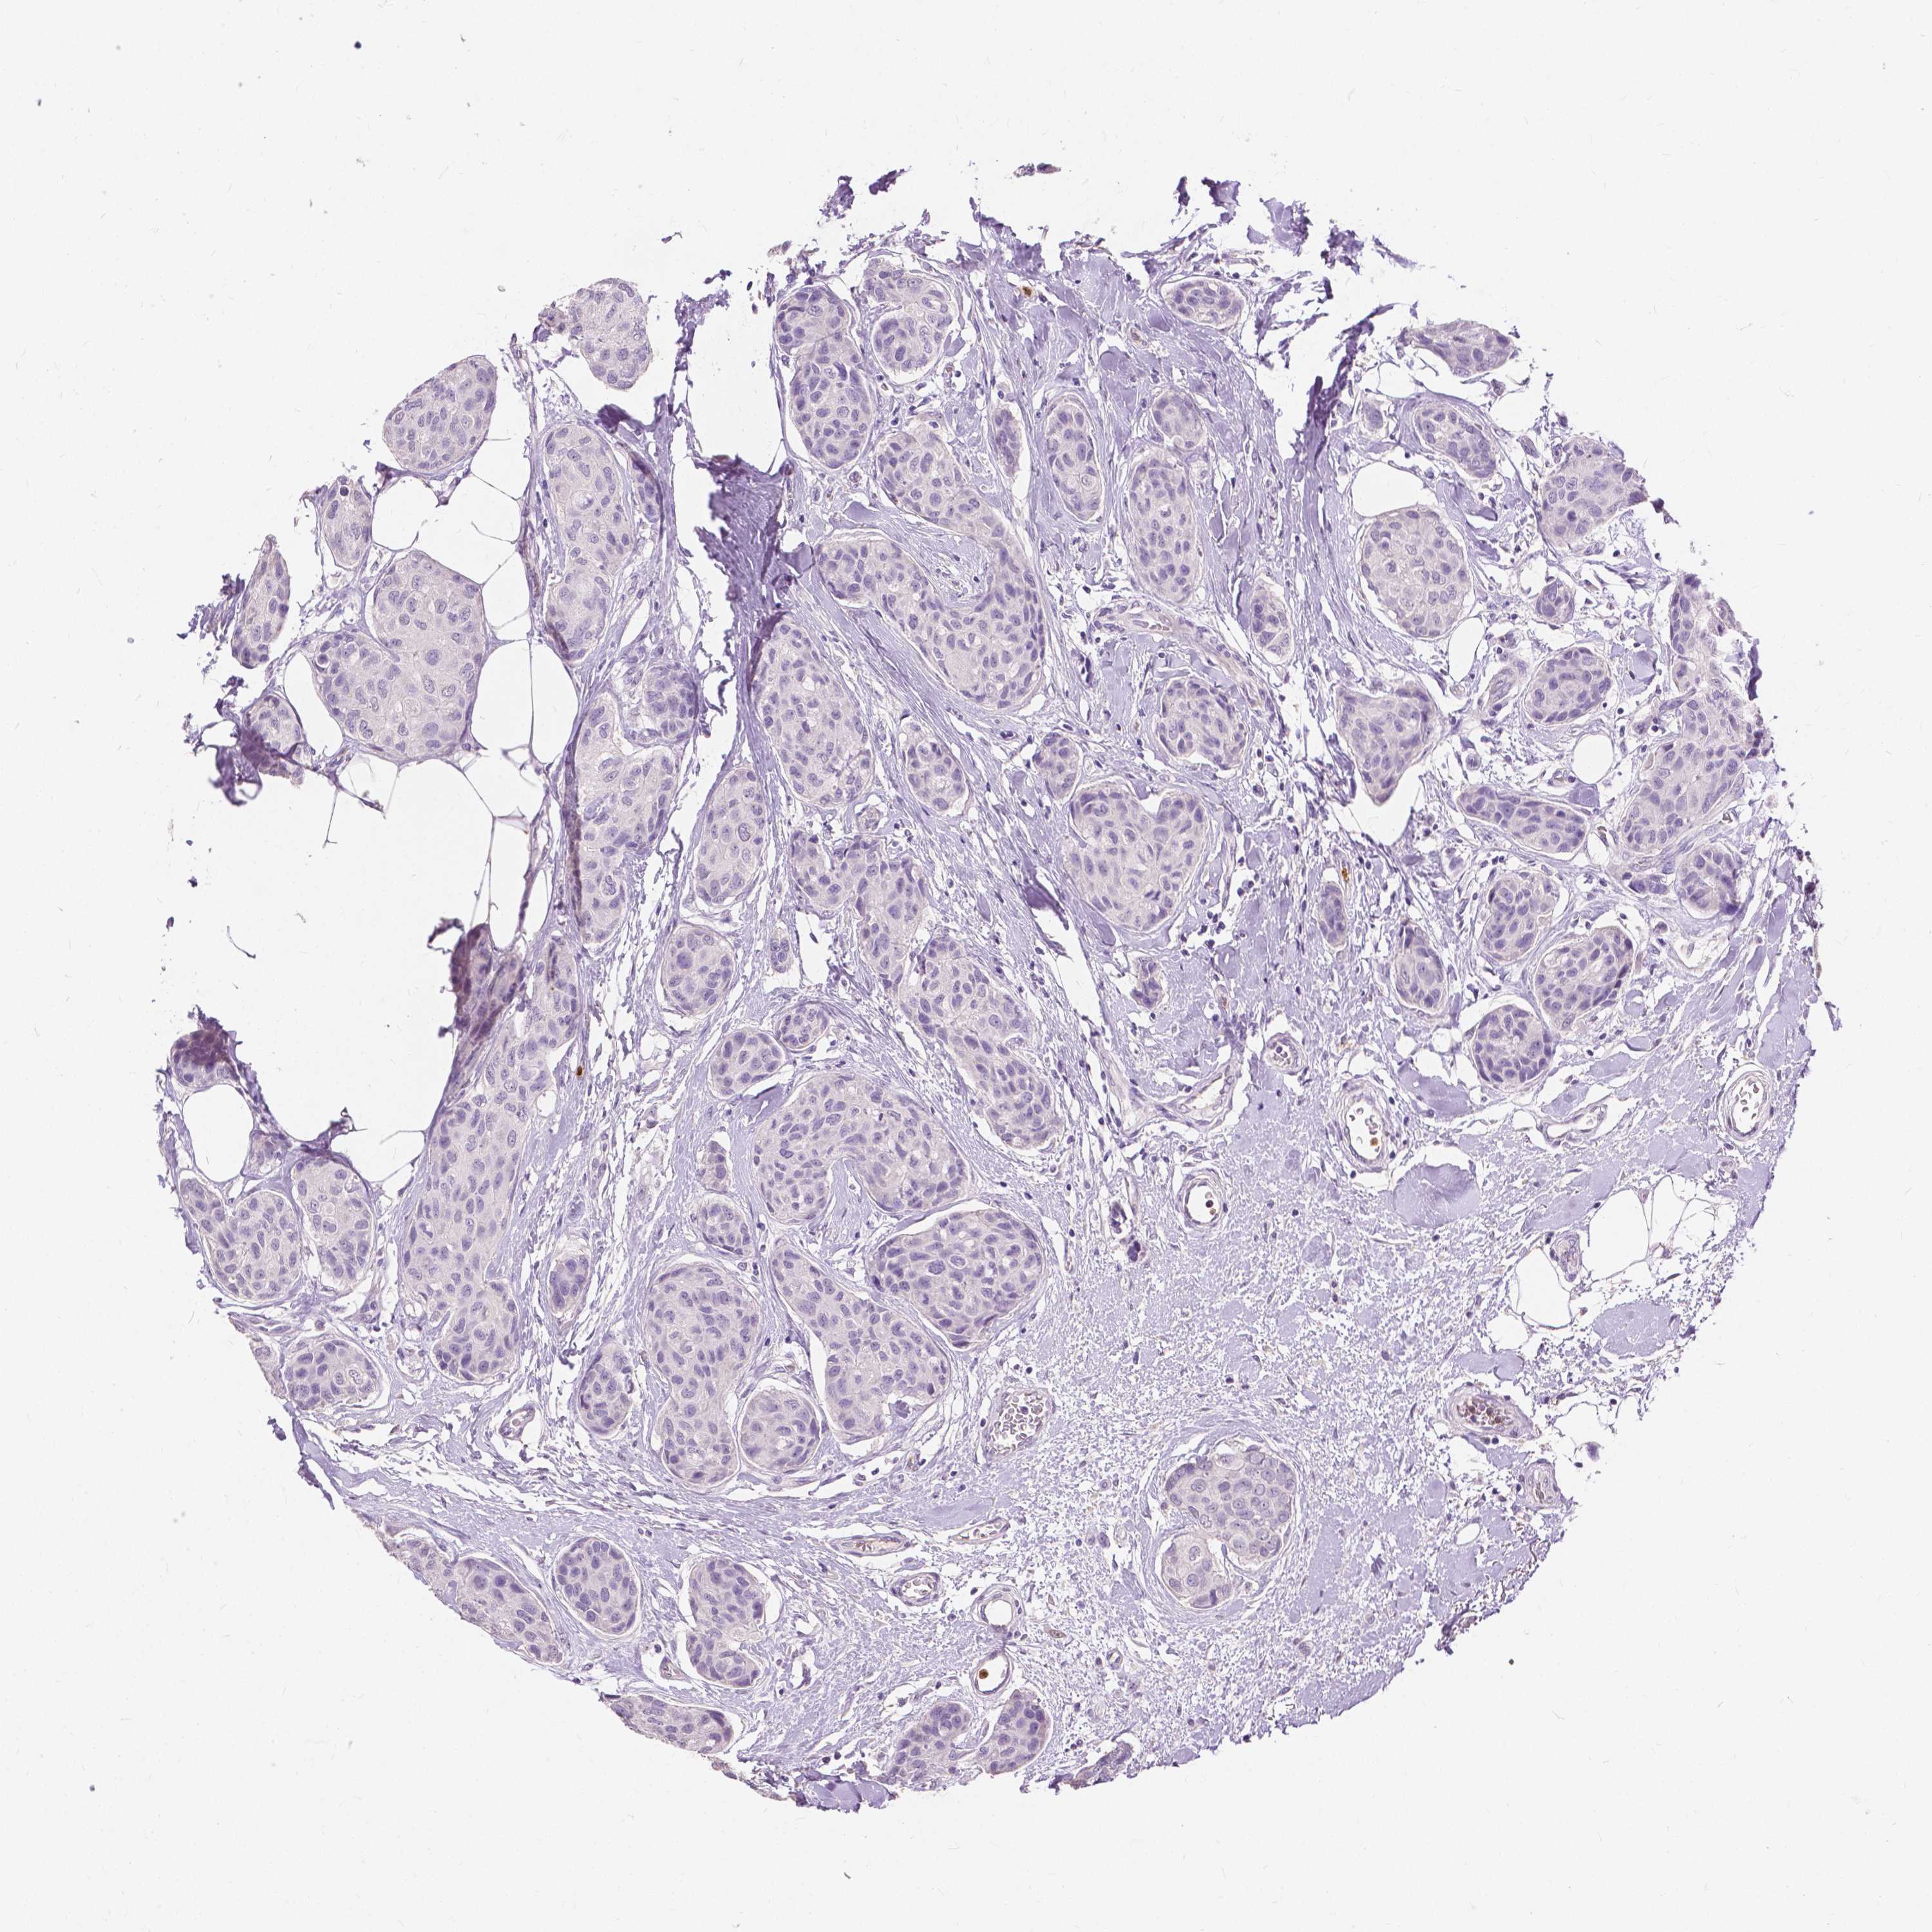

CANCER BREAST CANCER Show tissue menu

BRCA TCGA BRCA VALIDATION PROTEIN EXPRESSION

ANTIBODIES

AND

VALIDATION